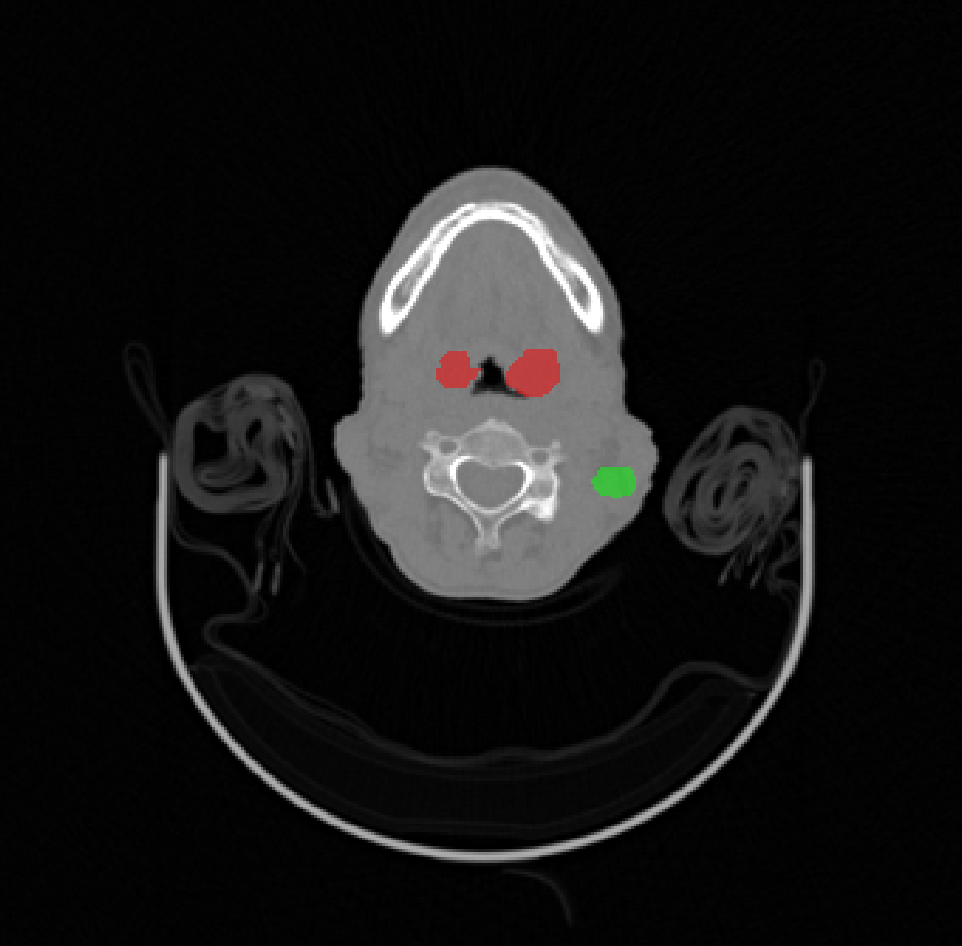

Head and neck tumor segmentation challenge (HECKTOR) provides an opportunity for researchers to develop 3D algorithms for the segmentation of H&N primary tumors (GTVp) in 3D PET/CT scans. HECKTOR 2022 [2, 5] is a third edition of the challenge which consists of 883 cases (524 labeled cases were provided for training), each with 3D CT, 3D PET rigidly registered to a common frame, but at different resolutions. The ground truth 3D labels provide dense 3D annotations of 2 structures: gross tumor volumes of the primary tumors (GTVp) and lymph nodes (GTVn). Generally PET images highlight tumor activity at a lower resolution, whereas CT images provide higher resolution anatomical details. In case of the radiotherapy treatment, the tumor delineation must be done in the CT coordinate system, which which will be used to calculate the radiation dose to the tumor region. The HECKTOR22 challenge also includes the second task of outcome prediction, but here we focus solely on the segmentation task. The data used in this challenge comes from multiple institutions (9 centers in total), including 4 centers in Canada, 2 centers in Switzerland, 2 centers in France, and 1 center in the United States for a total of 883 patients with annotated GTVp and GTVn [2, 5].

The ground truth labels usually include a single mass of the primary tumor (but in some cases it was absent completely or had two components), and several connected components of the annotated lymph nodes. An example case of CT and the corresponding PET image with ground-truth overlays is shown in Figures 1 and 2.